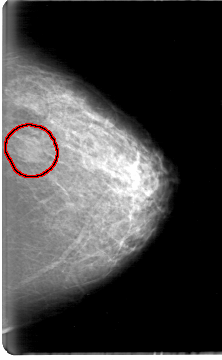

D_4058_1.LEFT_MLO

LEFT_MLO LINES 5386 PIXELS_PER_LINE 3736 BITS_PER_PIXEL 12 RESOLUTION 43.5 OVERLAY

FILE: D_4058_1.LEFT_MLO.OVERLAY

TOTAL_ABNORMALITIES 1

ABNORMALITY 1

LESION_TYPE MASS SHAPE OVAL MARGINS OBSCURED

ASSESSMENT 0

SUBTLETY 3

PATHOLOGY BENIGN

TOTAL_OUTLINES 1

BOUNDARY